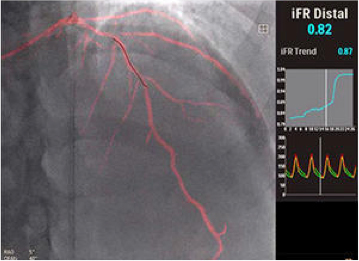

Coronary Intervention 誌Vol.14 No.13に掲載されました。

「Coronary Intervention誌」は心血管インターベンション治療を行う医師に最も読まれている医学専門誌です。

当院の華岡院長は「Coronary Intervention誌」の編集委員として,日本全国のインターベンション治療医に最新情報を発信しています。